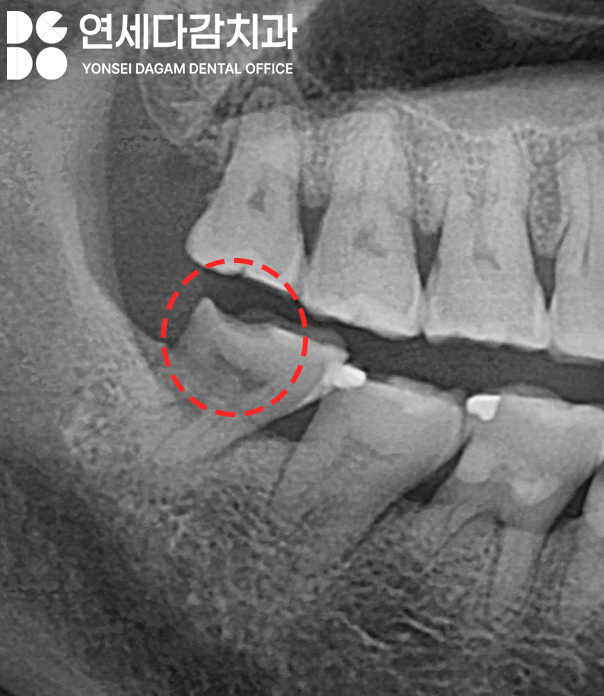

무엇보다 교모가 심하게 진행된 경우에는

치아가 구조가 점차 약해지면서

문정역 치과 에서 표시한

부위처럼 금이 가거나

파절될 위험이 높아집니다.

마치 금속 부품이 계속 마찰을 받으면

표면이 거칠어지고

결국 균열이 생기는 것처럼,

치아도 지속적인 압력을 받으면

구조적 손상이 일어납니다.

TFO라고 불리는 외상성 교합에 의해

치수염이 발생하기도 합니다.

심한 교모로 치아가 파절된 경우

신경에는 문제가 없는지

정밀한 검사를 한 뒤,

문제가 없다면

신경치료 없이 크라운 치료를 진행하여

치아의 형태와 기능을 회복시킵니다.